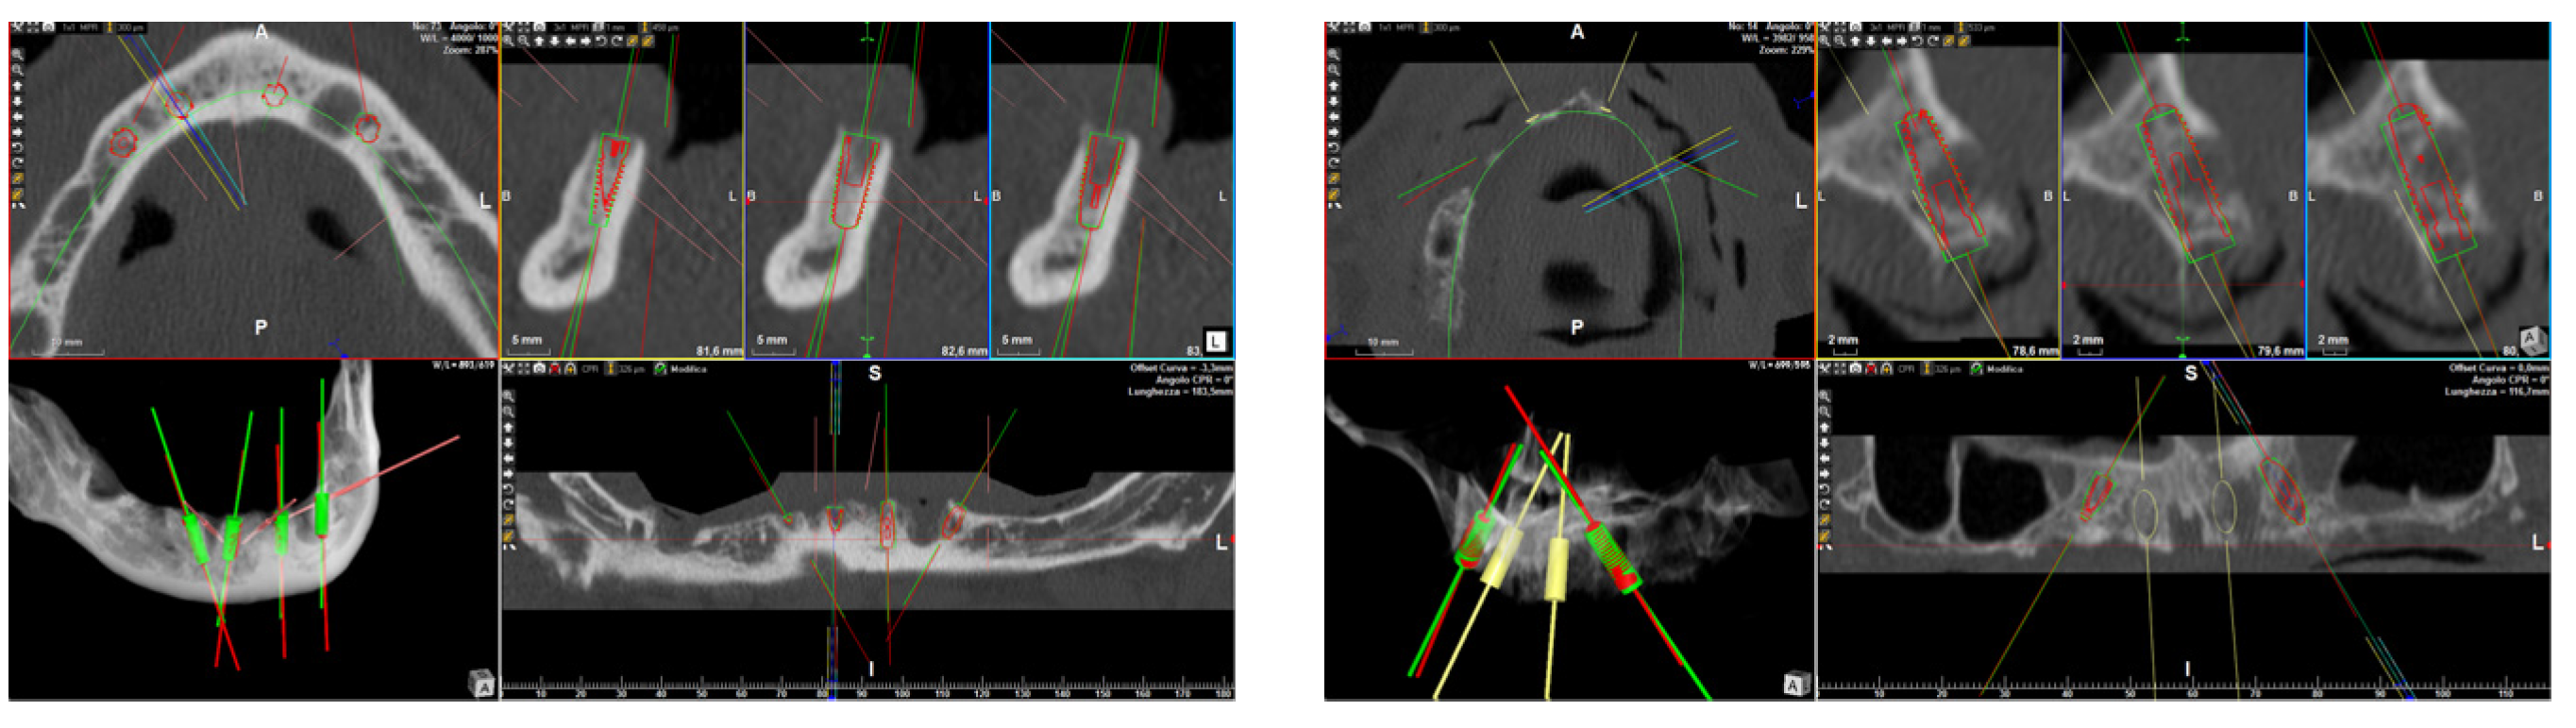

Accuracy evaluation: The same procedures as those described in a previous article were carried out [6]. In brief, a postsurgical CBCT scan was conducted with the same apparatus and settings as the preoperative radiological exam. The pre- and post-operative CBCT scans were then overlapped using a specific algorithm in order to compare the virtually planned and actual implant positions and to determine the accuracy level. More in detail, the protocol comprised different phases: (1) extrapolation of the STL files of the bone acquired from the pre-operative CBCT scan via a segmentation process and converting data from DICOM to STL format by means of dedicated software (RealGUIDE 5.0, 3DIEMME, Como, Italy, and Mimics, Materialise, Leuven, Belgium); (2) extrapolation of the STL files of the bone and the final implant positions acquired from the pre-operative CBCT scan via the same segmentation process used above; (3) overlapping of the bone structures retrievable in both pre- and post-operative CBCT scans, which remained unchanged following the surgical procedure (Figure 3). This was an essential aspect as it allowed placing the pre-operative virtual implants planned in the software and the post-operative real implants in the same reference system (GeoMagic Wrap 12, Geomagic Inc., Morrisville, NC, USA). (4) Due to the fact that, in the post-operative CBCT scan, the implants were often surrounded by metal artifacts that yielded low resolutions, each implant was replaced with a high-resolution STL file of the implant retrieved from a digital library available in the planning software. (5) The 3D pre- and post-operative positions of each implant were overlapped, and subsequent calculations of the variables of interest were carried out by means of dedicated software (Rhinoceros 5, Robert McNeel & Associates, Seattle, WA, USA). Three deviation parameters were recorded between each planned and placed fixture: linear deviation (mm) at the implant head and apex and angular deviation (°) of the implant long axis. All measurements were conducted using dedicated software (3Diagnosys, RealGUIDE 5.0, 3DIEMME, Como, Italy).

Figure 3. Accuracy evaluation between the planned (red) and real (green) implant positions.